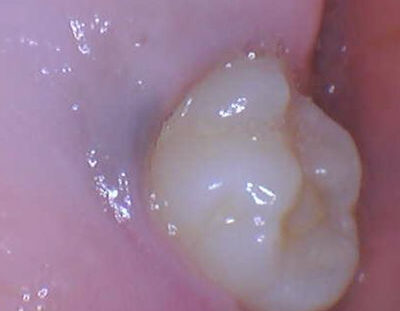

During a recall exam, a pediatric dentist noted a bluish-colored lesion on the gumline, lingual to tooth #3.